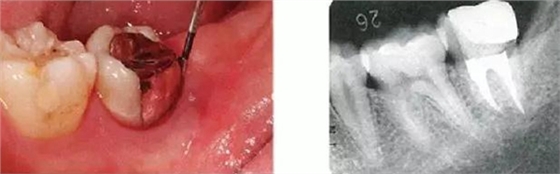

●智齒拔牙引起的附著喪失

27歲的女性,下頜左側(cè)智齒冠周炎引起腫脹而來(lái)院的患者。左下7的遠(yuǎn)中與智齒牙冠部相連的地方有6mm的牙周袋,并伴有出血和排膿。

智齒拔牙2個(gè)月后的狀態(tài),由于拔牙是的左下7的遠(yuǎn)中牙槽骨大量缺損。

智齒拔牙14個(gè)月后的狀態(tài)。X片上可觀察到,左下7遠(yuǎn)中側(cè)牙槽骨再生。但是仍然存在6mm的牙周袋和牙周出血。